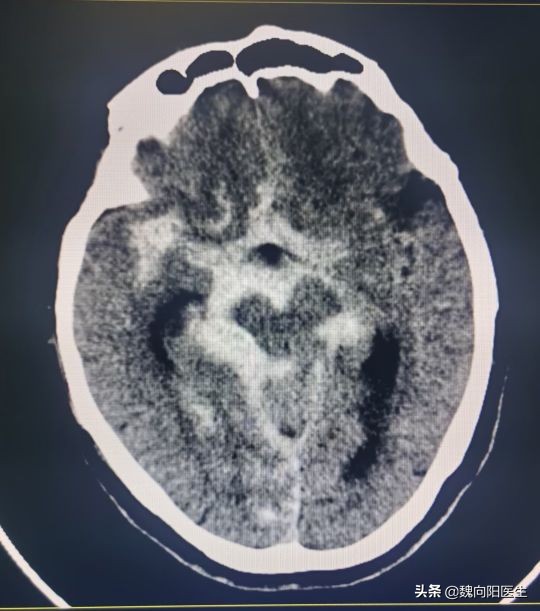

赶紧拉到医院,头CT提示:蛛网膜下腔出血。

这可是一个要命的病,一般都是由于脑动脉瘤破裂所导致。

动脉瘤破裂之后,会涌出大量的新鲜血液,使大脑浸泡在血水当中。随时间的推移,这些血水会持续的毒害大脑,导致一系列的反应。

正常人的脑积液属于无色透明的,蛛网膜下腔出血之后,血液涌到脑室里面和蛛网膜下腔,与脑积液混合就会变成血红色。